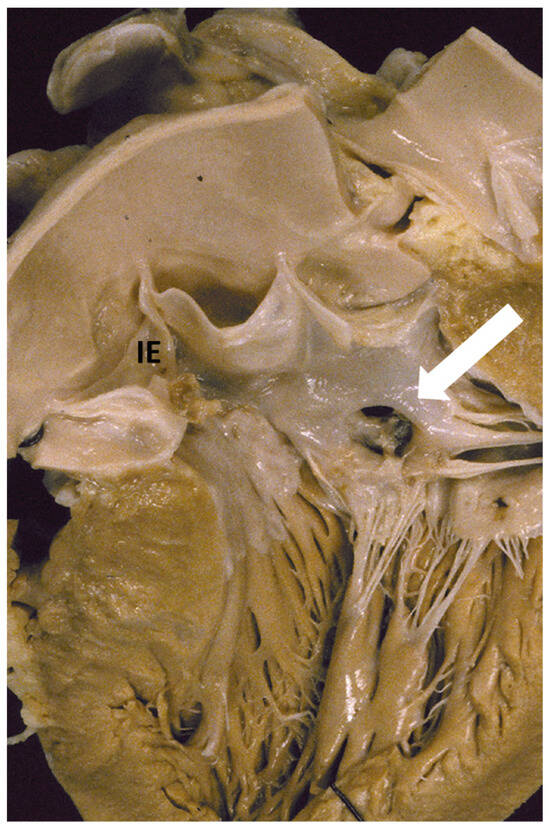

1. The Pathology Spectrum of Hypertrophic Cardiomyopathy